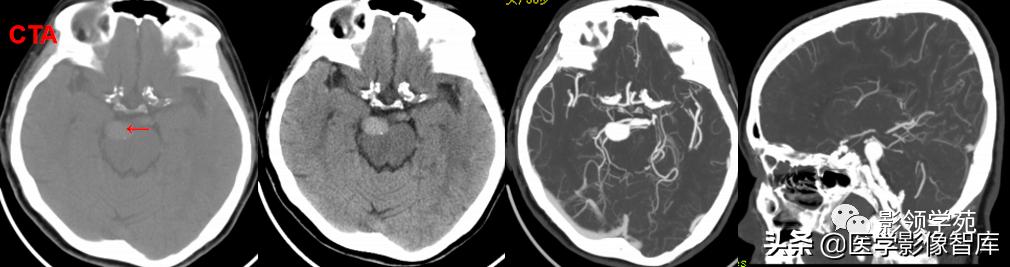

女 58岁,头晕、呕吐,桥脑右前方见一类圆形

高低混合(有血栓)T1及T2信号影,边界清楚、锐利。

明显不均匀强化(瘤内有血栓)。与基底动脉分界不清

头颅CTA:基底动脉起始部血管局部瘤样突起(宽基底),无占位效应。